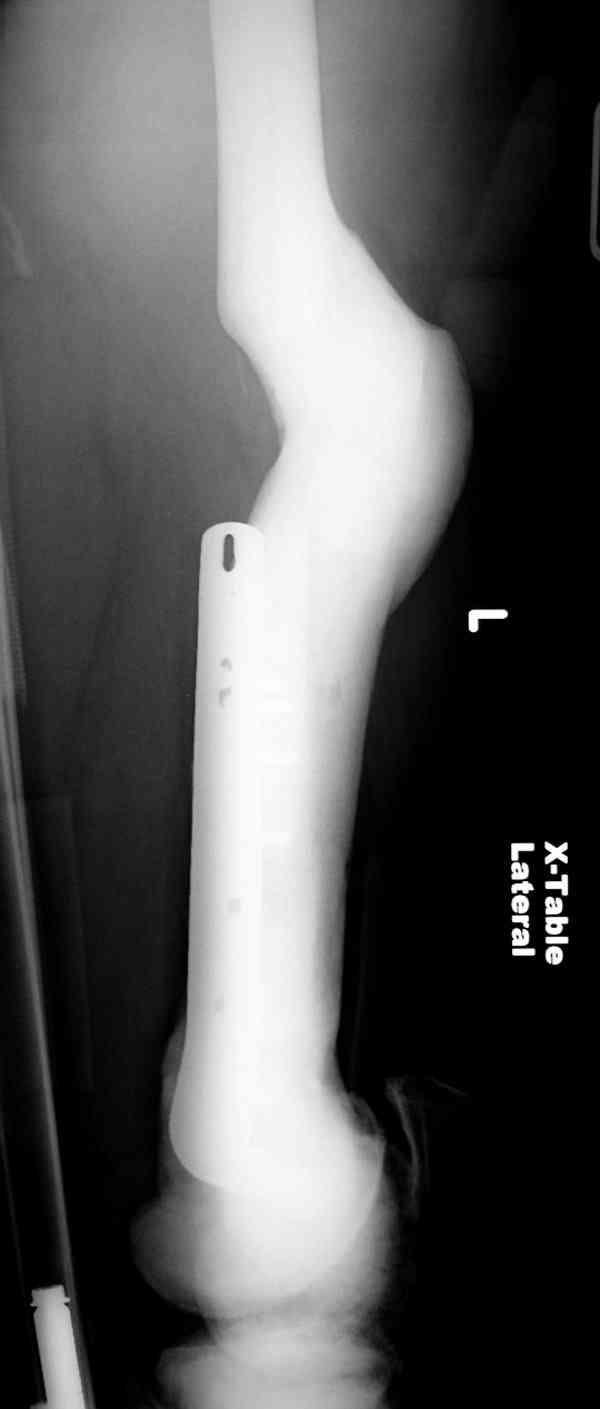

Не являюсь специалистом по костной патологии, но мне кажется, на ренгенограмме множественные мета-диафизарные образования напоминяющее змееподобных извилистых линии и периостеальные ламинирование очень напоминяет картину остеонекроза (инфаркта) костей, возможно связано с длительным применением стероидов.

При предоставлении дополнительных информации, сканнирования, МРТ и лабараторных данных можно уточнить предварительный диагноз, пока склонен к обширному костному инфаркту, и таких больных рекомендуем лечить сиптоматически.

слайды из прошлегодного случая.